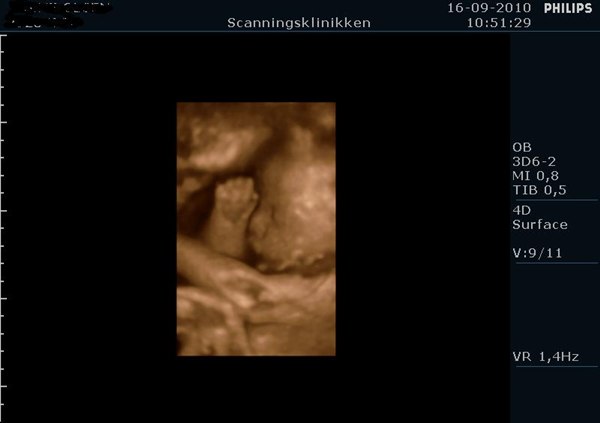

Det så bare så skægt ud med den hikke, og tror nok det kom med på dvden i starten hvor hun lavede 2D...

Men ja, hun ser bare så dejlig ud, og vil bare så gerne have hende ud med det samme, men hun skal jo lige blive lidt længere alligevel